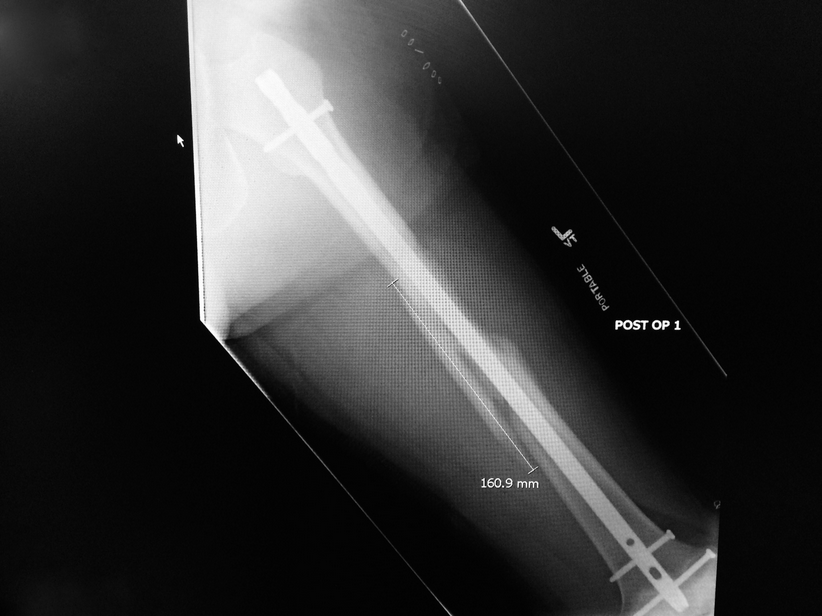

By the time they got to my ski boots, I was already off in La La Land. I slept the entire ambulance ride down to Vancouver General Hospital and was in the operating room that very evening. Despite the avalanche cutting off my years of good luck, I had one remaining bit of good fortune: I was operated on by Dr. Blachut, a true craftsman in the orthopedic field. My stay in the orthopedic ward lasted for two days. The entire time, getting out and going home was my top priority: you can get sick in hospitals!

So far, my recovery seems to be going well. I would like to thank those at the scene for their help, the staff at the Whistler Medical Clinic for their care, the ambulance crews for their great work, the Orthopedic Department at Vancouver General for a new titanium femur, and my partner Suze for her care and nursing of a spoiled patient.